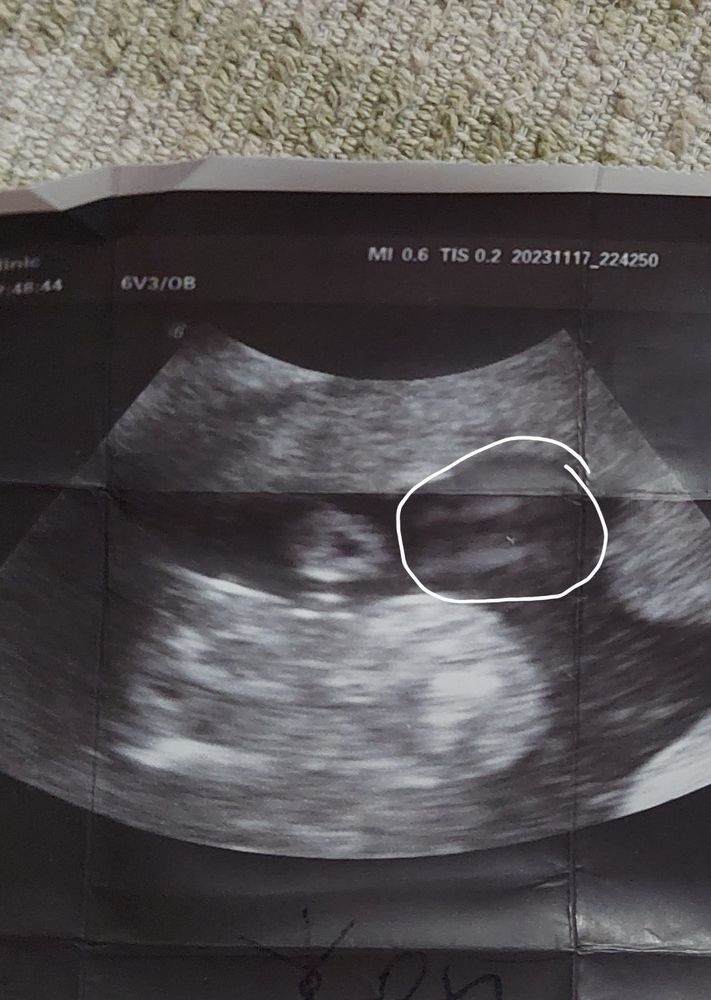

Узист сделал фото очень близко, трансвагинально ,прям этого места, но что то мне кажется что это не девочка. Ракурс " сидение на попе " и максимально близко сделано фото. Вот если у вас есть такой же ракурс близко то покидайте.

Юлия Перминова, у вас фото не супер четкое, но то, что вы обвели - похоже на девочку

Северянка, на оборот фото достаточно четкое и очень приближено, прям так сказать пирожок чуть ли не на пол фото.

Ну точно не девочка, если я конечно правильно понимаю положение) У девочек там две полосочки при таком ракурсе

Кристина( рисую на одежде ), половые губы, 2 полосочки?

Я обвела то что назвали половыми губами.